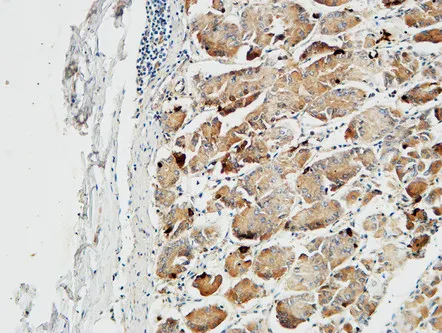

Glut4 Rabbit Polyclonal Antibody

Cat: APRab11504

Size1:50μl Price1:$118

Size2:100μl Price2:$220

Size3:500μl Price3:$980

Size2:100μl Price2:$220

Size3:500μl Price3:$980